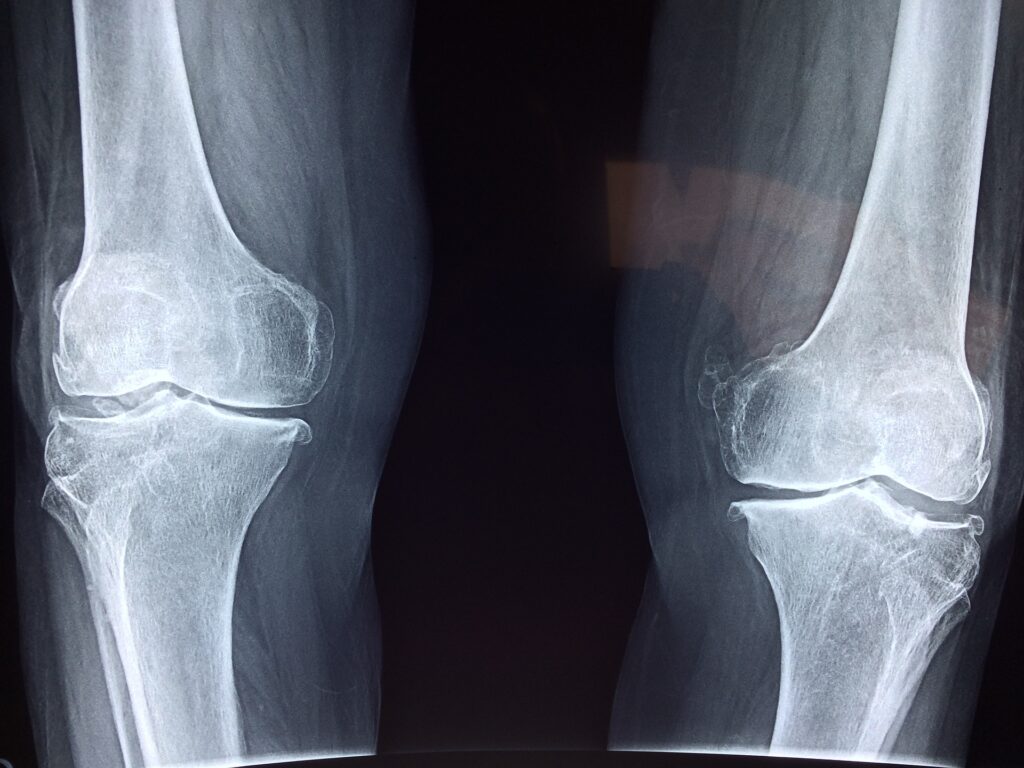

Specijalista fizijatar ili ortoped mogu postaviti dijagnozu na osnovu anamneze i pregleda vašeg kolena. Ukoliko fizijatar proceni da je potrebno posla će vas na dodatnu dijagnostiku (radiografija kolena, magentna rezonanca ili ultrazvuk zglobova.)

artroza kolena

Kod gonartroze ultrazvuk zglobova može pokazati prisustvo tečnosti u zglobu, stanje hrskavice, prisustvo osteofita i Bekerove ciste. Jednako kao magnetna rezonanca, ultrazvuk zglobova ima naročtio veliki značaj u ranim stadijumima artroze kolena.